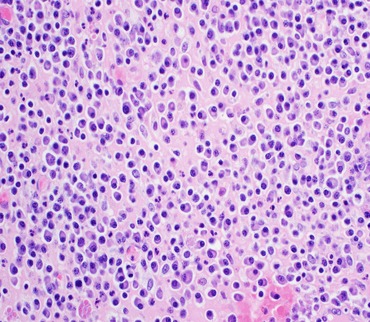

Our Proficiency Testing Schemes

Our Proficiency Testing Schemes

The robust external quality assurance for medical laboratories